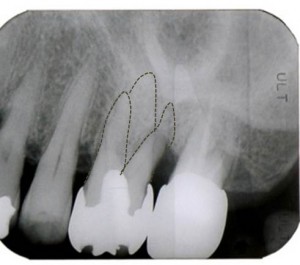

X線写真です。歯根が3本あることが分ります。

以下の写真は、②の歯根の骨吸収が進行したため1根のみ抜歯を行いました。残りの①と③の歯根に対して土台を立てブリッジを装着しました。

①と③の間は歯間ブラシで清掃できる環境となっています。